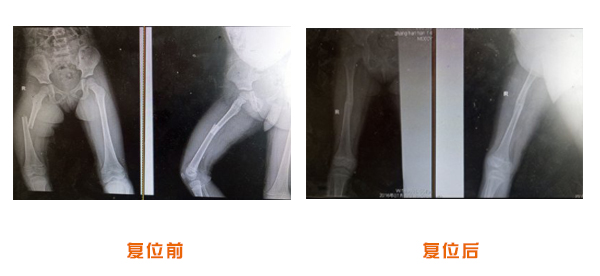

尺橈骨克雷氏骨折治療前后